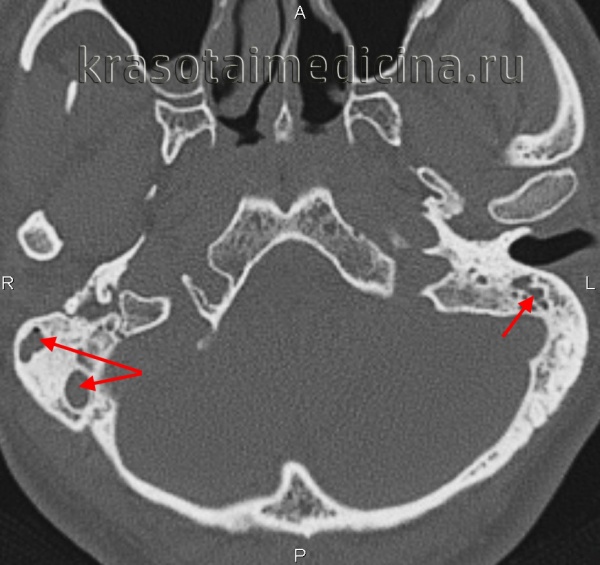

• Костная КТ:

о Снижение пневматизации СУ-СО

о Вариабельные эрозии трабекул и кортикального слоя (КТ признак сливного отомастоидита)

о Минимальная или значительная деструкция кортикального слоя сразу же под абсцессом:

- Наружный кортекс сосцевидного отростка - поднадкостничный абсцесс

- Кортикальный слой вершины сосцевидного отростка → абсцесс Бецольда

- Крыша сосцевидной пещеры → эпидуральный абсцесс или абсцесс височной доли

- Медиальный кортикальный слой сосцевидного отростка — эпидуральный или мозжечковый абсцесс

(Справа) При аксиальной КТ височной кости у этот же пациента определяется снижение пневматизации среднего уха и ячеек сосцевидного отростка, наряду с эрозией кортикального слоя сосцевидного отростка (сзади) и слуховых косточек, сопоставимой с отомастоидитом и холестеатомой, что и было подтверждено при операции.